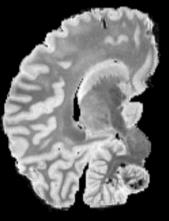

In neuroimaging, MRI tissue properties characterize underlying neurobiology, provide quantitative biomarkers for neurological disease detection and analysis, and can be used to synthesize arbitrary MRI contrasts. Estimating tissue properties from a single scan session using a protocol available on all clinical scanners promises to reduce scan time and cost, enable quantitative analysis in routine clinical scans and provide scan-independent biomarkers of disease. However, existing tissue properties estimation methods - most often $\mathbf{T_1}$ relaxation, $\mathbf{T_2^*}$ relaxation, and proton density ($\mathbf{PD}$) - require data from multiple scan sessions and cannot estimate all properties from a single clinically available MRI protocol such as the multiecho MRI scan. In addition, the widespread use of non-standard acquisition parameters across clinical imaging sites require estimation methods that can generalize across varying scanner parameters. However, existing learning methods are acquisition protocol specific and cannot estimate from heterogenous clinical data from different imaging sites. In this work we propose an unsupervised deep-learning strategy that employs MRI physics to estimate all three tissue properties from a single multiecho MRI scan session, and generalizes across varying acquisition parameters. The proposed strategy optimizes accurate synthesis of new MRI contrasts from estimated latent tissue properties, enabling unsupervised training, we also employ random acquisition parameters during training to achieve acquisition generalization. We provide the first demonstration of estimating all tissue properties from a single multiecho scan session. We demonstrate improved accuracy and generalizability for tissue property estimation and MRI synthesis.